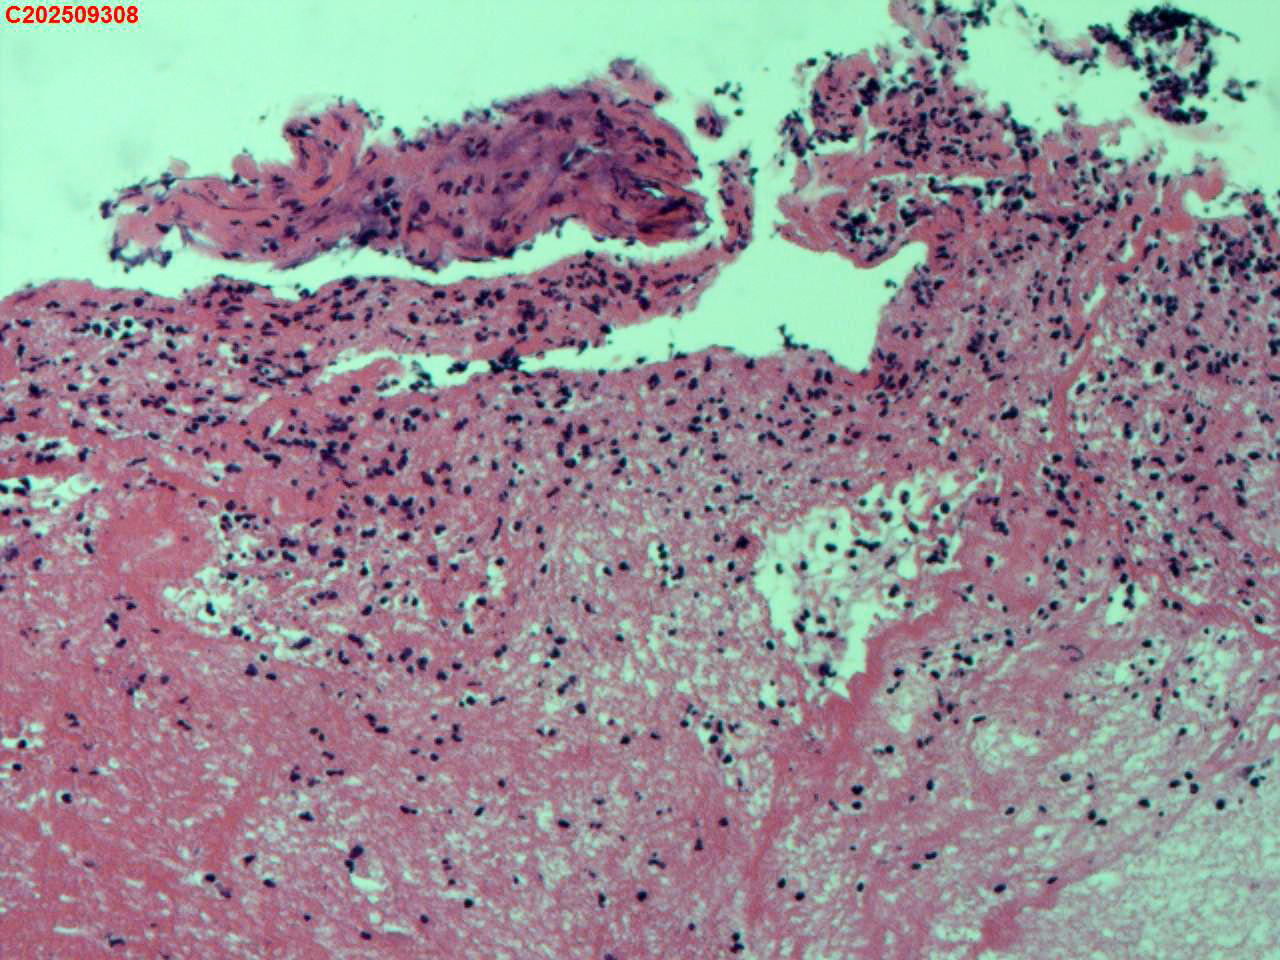

纤支镜咬检

肺结核、气管结核?

胸部CT:左肺多发病变及空洞考虑结核,请结合其他相关检查。右肺上叶小点状钙化灶。左肺门增大。

纤支镜:肉芽增生

送检粘膜鳞状上皮增生伴炎性渗出物及坏死物,建议做抗酸染色排除结核